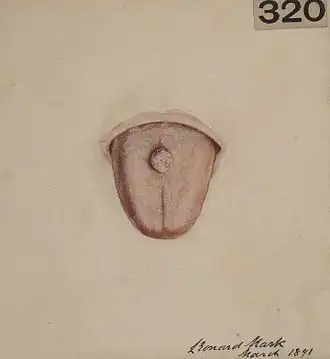

Linfangioma

| Linfangioma | |

| Linfangioma cavernoso na língua | |

- Linfangioma cavernoso

- Lesão única na derme que pode crescer durante a infância. Geralmente na cabeça, pescoço ou extremidades. Composto por canais linfáticos dilatados, um linfangioma cavernoso tipicamente desloca tecidos e órgãos adjacentes, podendo causar disfunção.